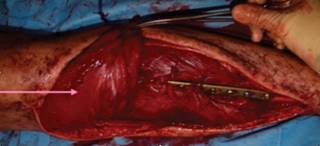

Surgery was performed by the orthopedic and plastic surgery team under general anesthesia. First a medial approach was performed accessing to the posterior compartment and identifying neuromuscular bundle. Extensive resection that included 15 cm of tibial shaft, surrounding soft tissue and 7 cm skin flap was performed securing intraoperative free edges. The tibial tuberosity and patellar tendon were left intact. Second a lateral approach over the fibula was performed, dissection of the peroneal artery and interosseous membrane, proximal and distal fibula osteotomy leaving 7 cm and 6 cm left correspondingly, followed by fibula tunneling to the anterior compartment (Figure 4).

Figure 4: A) Medial approach with proximal tibial and skin resection. B) Lateral approach with fibula graft, peroneal artery can be identified.